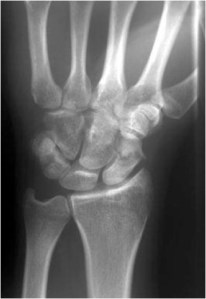

Carpal Fractures and Dislocations

Wrist fractures

Carpal & Metacarpal fractures/dislocations